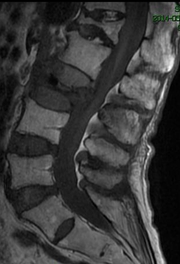

因:“腰椎骨折椎体成形术后2天”入院

患者因“脑卒中后遗症”在我中心康复治疗,于4月27日行走时滑倒腰部跌伤,当时即感疼痛,活动受限,到当地医院就诊,经CT等检查后,诊断为L3骨折,予卧床休息、口服活血化瘀及镇痛等对症治疗,患者自觉症状无改善,于6月03日在上级医院行椎体成形手术,2014年6月04日再次转入我中心继续康复治疗。患者入院时腰背部疼痛明显改善,并可下床活动。

神清,精神可,轮椅推入病房,精神略显紧张,发育正常,营养中等,呼吸平稳,查体合作,言语清晰,对答切题。全身皮肤粘膜无黄染,无皮疹、无淤斑、淤点,毛发分布正常,皮温正常、皮肤弹性正常,无肝掌。浅表淋巴结未及肿大。头颅大小正常,无畸形,眼睑无水肿,结膜无充血,眼球正常,无运动障碍,巩膜无黄染,角膜正常,双侧瞳孔等大等圆7.5px,对光反射正常。左侧鼻唇沟浅,左侧口角下垂,左侧额纹消失,耳廓正常,外耳道无脓性分泌物,乳突无压痛,双侧听力正常。鼻外形正常,鼻道畅,鼻中隔无偏曲,鼻旁窦无压痛。口唇红润无绀,口腔粘膜正常,舌正常,伸舌居中,牙龈无肿胀出血,咽无充血,双侧扁桃体未见肿大,声音正常。颈软,无抵抗,脑膜刺激征阴性,气管居中,颈静脉无充盈,双侧甲状腺未及肿大,无压痛。胸廓无明显畸形,乳头对称,双侧呼吸运动对称,语颤相等,叩诊清音,双肺呼吸音粗,未及明显干湿啰音。心前区未见异常隆起,心尖搏动位于左第5肋锁骨中线内12.5px,未及震颤,心相对浊音界正常。心率80次/分,律齐,各瓣膜听诊区未闻及病理性杂音。未及水冲脉、股动脉枪击音。腹平,未见腹壁静脉曲张,未见肠型蠕动波,腹软,无压痛、反跳痛,肝脾肋下未及,肾未触及,全腹未触及包块,肝肾区无叩痛,移动性浊音阴性,肠鸣音正常,5次/分。脊柱胸腰段后凸畸形,活动度轻度受限,棘突无明显叩痛,双下肢无水肿。四肢肌力正常,关节无畸形。双下肢感觉正常。

入院诊断:(1)腰椎骨折术后